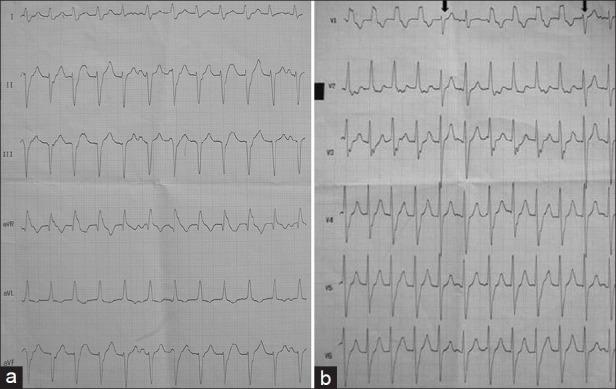

Intraoperative interfascicular ventricular tachycardia: A rare occurrence.

Indian J Anaesth. 2014 Jan;58(1):76-8. doi: 10.4103/0019-5049.126807.